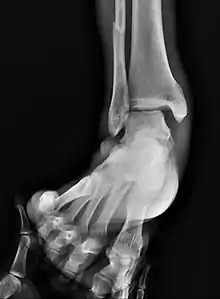

![]() | |

| Fracture of both sides of the ankle with dislocation as seen on anteroposterior X-ray. (1) fibula, (2) tibia, (arrow) medial malleolus, (arrowhead) lateral malleolus | |